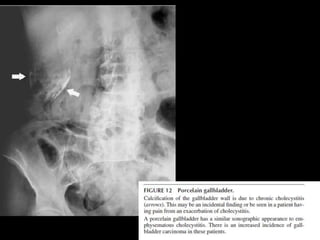

• ULTRASONOGRAPHY : bright echogenic

crescent in the gallbladder fossa with dirty

shadowing and ring down artifacts.

– Similar:

• Contracted stone-filled gallbladder (WES)

• Porcelain gallbladder w/ calcified wall due to chronic

cholecystitis

• CONFIRMATION:

– Abdominal rx or CT

BEST INITIAL TEST? •ULTRASONOGRAPHY : bright echogenic crescent in the gallbladder fossa with dirty shadowing and ring down artifacts. – Similar: • Contracted stone-filled gallbladder (WES) • Porcelain gallbladder w/ calcified wall due to chronic cholecystitis • CONFIRMATION: – Abdominal rx or CT